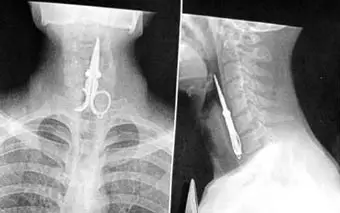

Китайские хирурги из города Путянь спасли жизнь мужчины, случайно проглотившего девяти-сантиметровые маникюрные ножницы, сообщает Telegraph. 27-летний Лин Кон (Lin Kong) одолжил у своего друга ножницы, чтобы воспользоваться ими в качестве зубочистки. Знакомый Кона рассказал ему шутку, в то время когда тот чистил зубы. Кон рассмеялся, ножницы выскользнули у него из рук и провалились прямо в горло. Рентгеновский снимок показал, что ножницы полностью дошли до пищевода. Хирурги смогли оперировать только под местным наркозом, так как общий наркоз расслабил бы мышцы мужчины, и прибор провалился бы глубже. Вся операция заняла 30 минут. Врачи многих стран часто извлекают из желудков пациентов различные предметы. Медики из научно-медицинского центра университета Теннесси обнаружили в желудке пациентки целую "копилку". Один из ее родственников сообщил, что она проглотила несколько монеток. В результате операции специалисты обнаружили 585 пенни, 17 монет в пять центов, 12 монет в десять центов, восемь монет в 25 центов и одну немецкую марку.